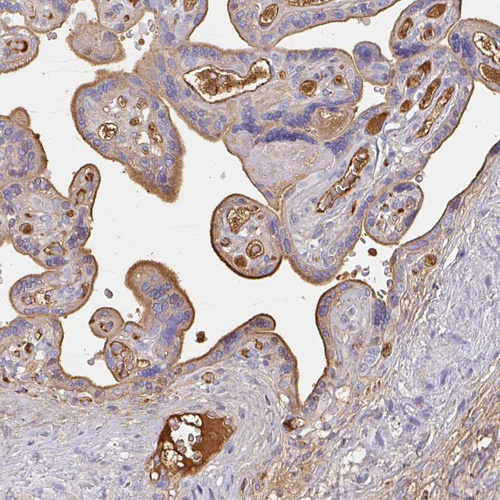

Immunohistochemical staining of human kidney, pancreas, placenta and prostate using Anti-ALB antibody HPA031025 (A) shows similar protein distribution across tissues to independent antibody HPA031024 (B).